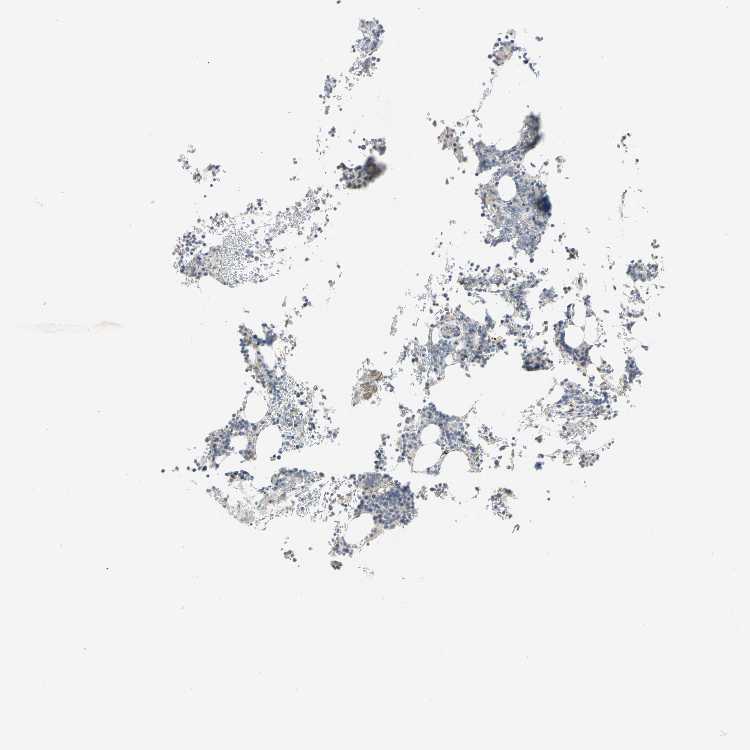

BONE MARROW - Antibody stainingi

Antibody staining in the annotated cell types in the current human tissue is reported as not detected, low, medium, or high, based on conventional immunohistochemistry profiling in selected tissues. This score is based on the combination of the staining intensity and fraction of stained cells.

Each image is clickable and will lead to virtual microscopy that enables deeper exploration of all samples and also displays staining intensity scores, fraction scores and subcellular localization as well as patient and tissue information for each sample.

Antibody HPA004098

Hematopoietic cells Low